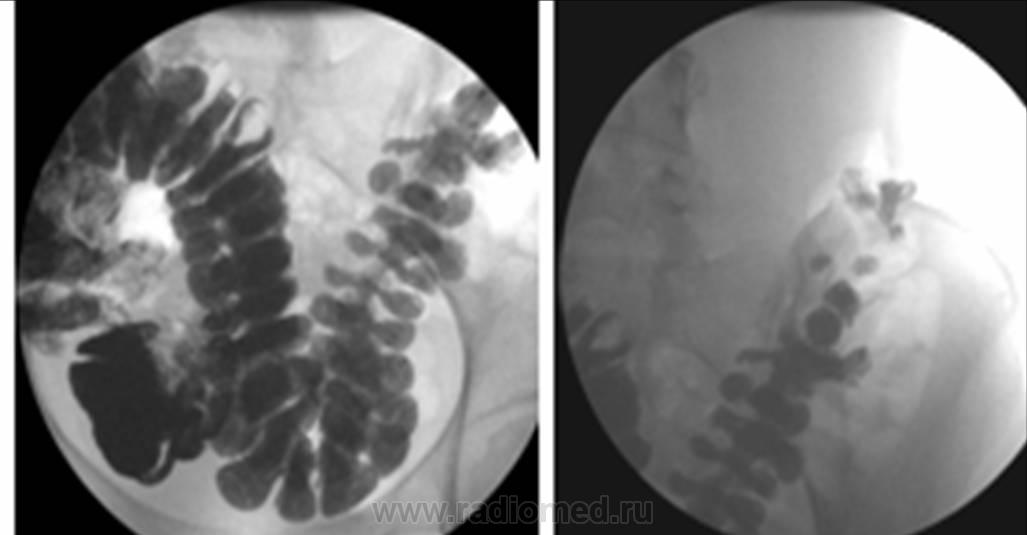

Молодая женщина. Астенического телосложения (если не сказать - кахектична). Жалобы на постоянные боли в животе и запоры. Ваше мнение?

В продолжение темы....еще однин "одуванчик".....естественно - с запорами....